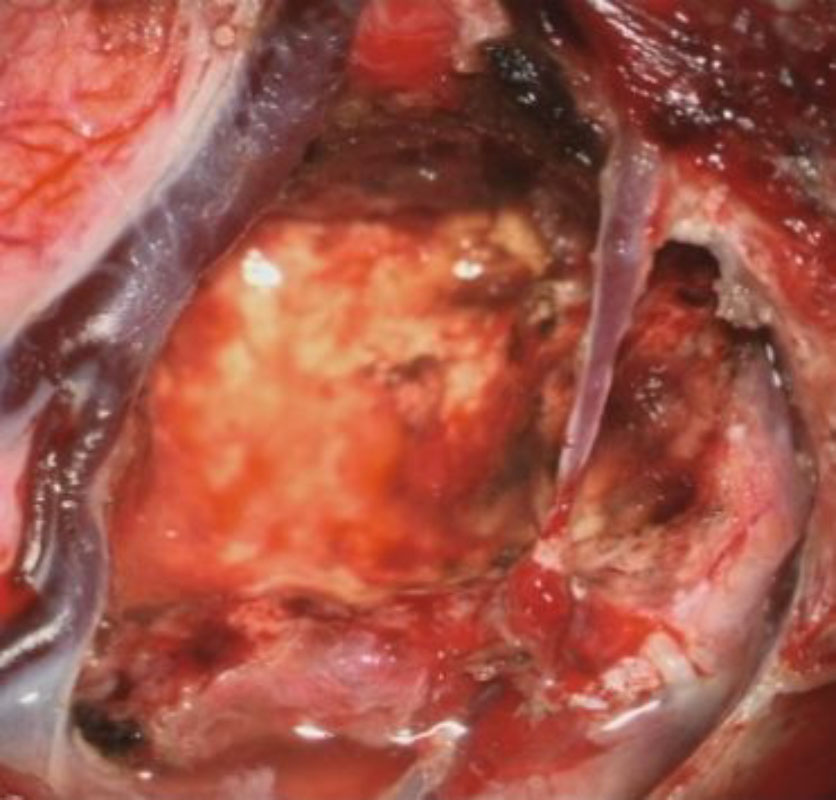

No.’25_26 手術前1

No.’25_26 手術前2

No.’25_26 摘出 前

No.’25_26  摘出 中

No.’25_26 摘出 後

624

'25年4月

70代

後頭葉膠芽腫

頭蓋内腫瘍摘出術